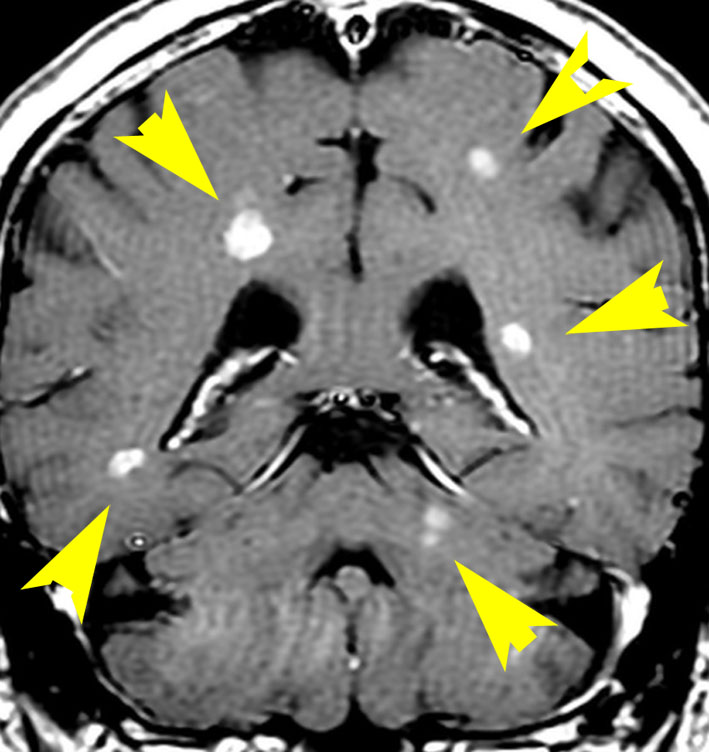

がんの脳転移 開かれる治療の扉 医療プレミア特集 毎日新聞 医療

転移性脳腫瘍の放射線治療と認知機能 放射線を脳にかけると ぼける